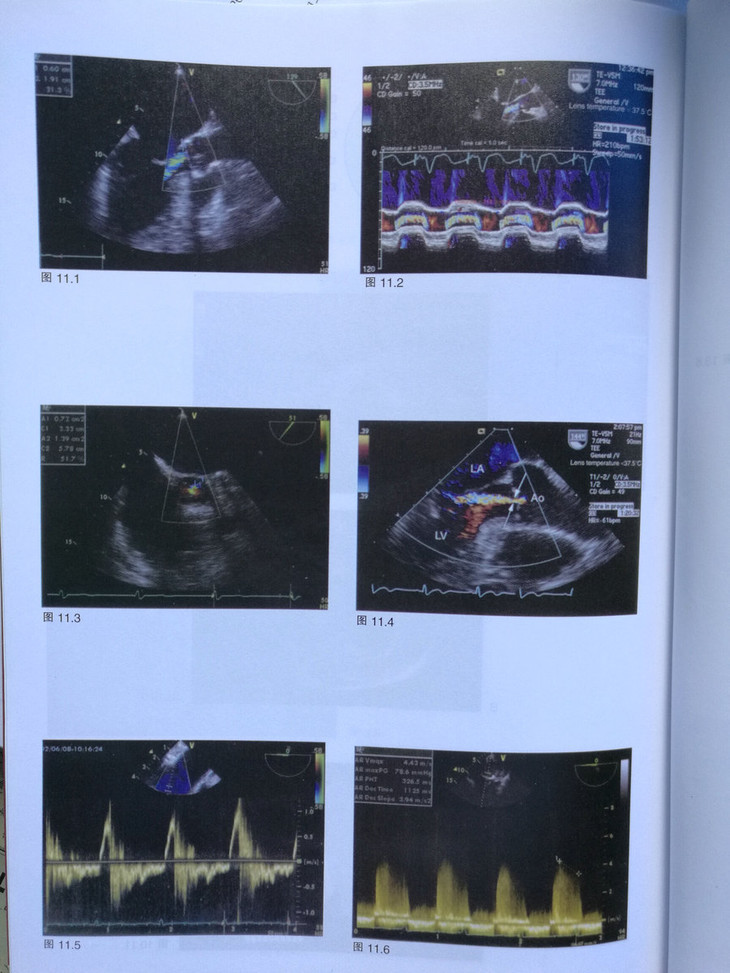

第11章 主动脉瓣关闭不全